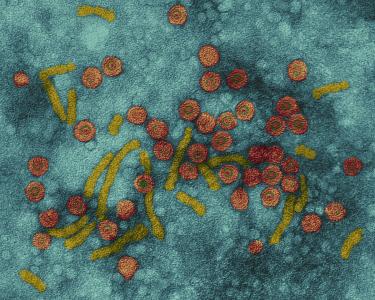

关于白血病靶向药——格列卫的介绍...

格列卫(甲磺酸伊马替尼)疗效的判断...

伊马替尼(格列卫)的不良反应有哪些...

伊马替尼(格列卫)耐药了怎么办?...